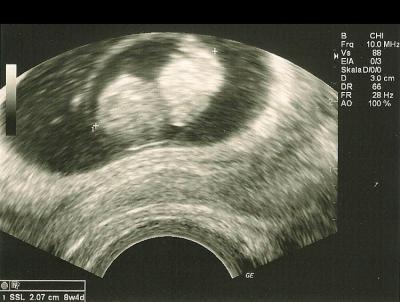

Hallo zusammen, ich war ja heute beim US. Mein Würmchen ist 2,07 cm groß und hat grade geschlafen. Herzchen hat aber eifrig geschlagen und ich bin mal wieder beruhigt.

Bild zu US-Termin heute - Forum für April - Mamis